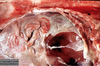

What are the molecular and morphologic changes of the image? ( MDx)

Clinical history and signs: 3 week old puppy, anorexia, dypsnea, abd pain upon palpation, normal rectal temperature

Multifocal, acute renal necrosis and hemorrhage or necrohemorrhagic nephritis

What is the etiology?

Clinical history and signs: 3 week old puppy, anorexia, dypsnea, abd pain upon palpation, normal rectal temperature

Canine herpesvirus-1 (CHV-1)

- red spots are from the virus targeting endothelium

What is the pathogenesis?

Clinical history and signs: 3 week old puppy, anorexia, dypsnea, abd pain upon palpation, normal rectal temperature

Transmission CHV-1 to pup at birth >incubation period of up to 1 week > virus replicates at temperature lower than 37C (98.6F) > endothelial cell tropism > multifocal necrosis in numerous organs